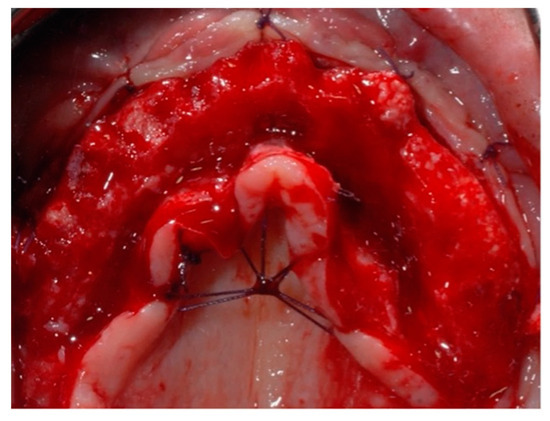

Figure 6. Final sutures (occlusal view).

Figure 8. Clinical view (frontal in (a) and occlusal in (b)) of the upper maxillary arch before implant placement.